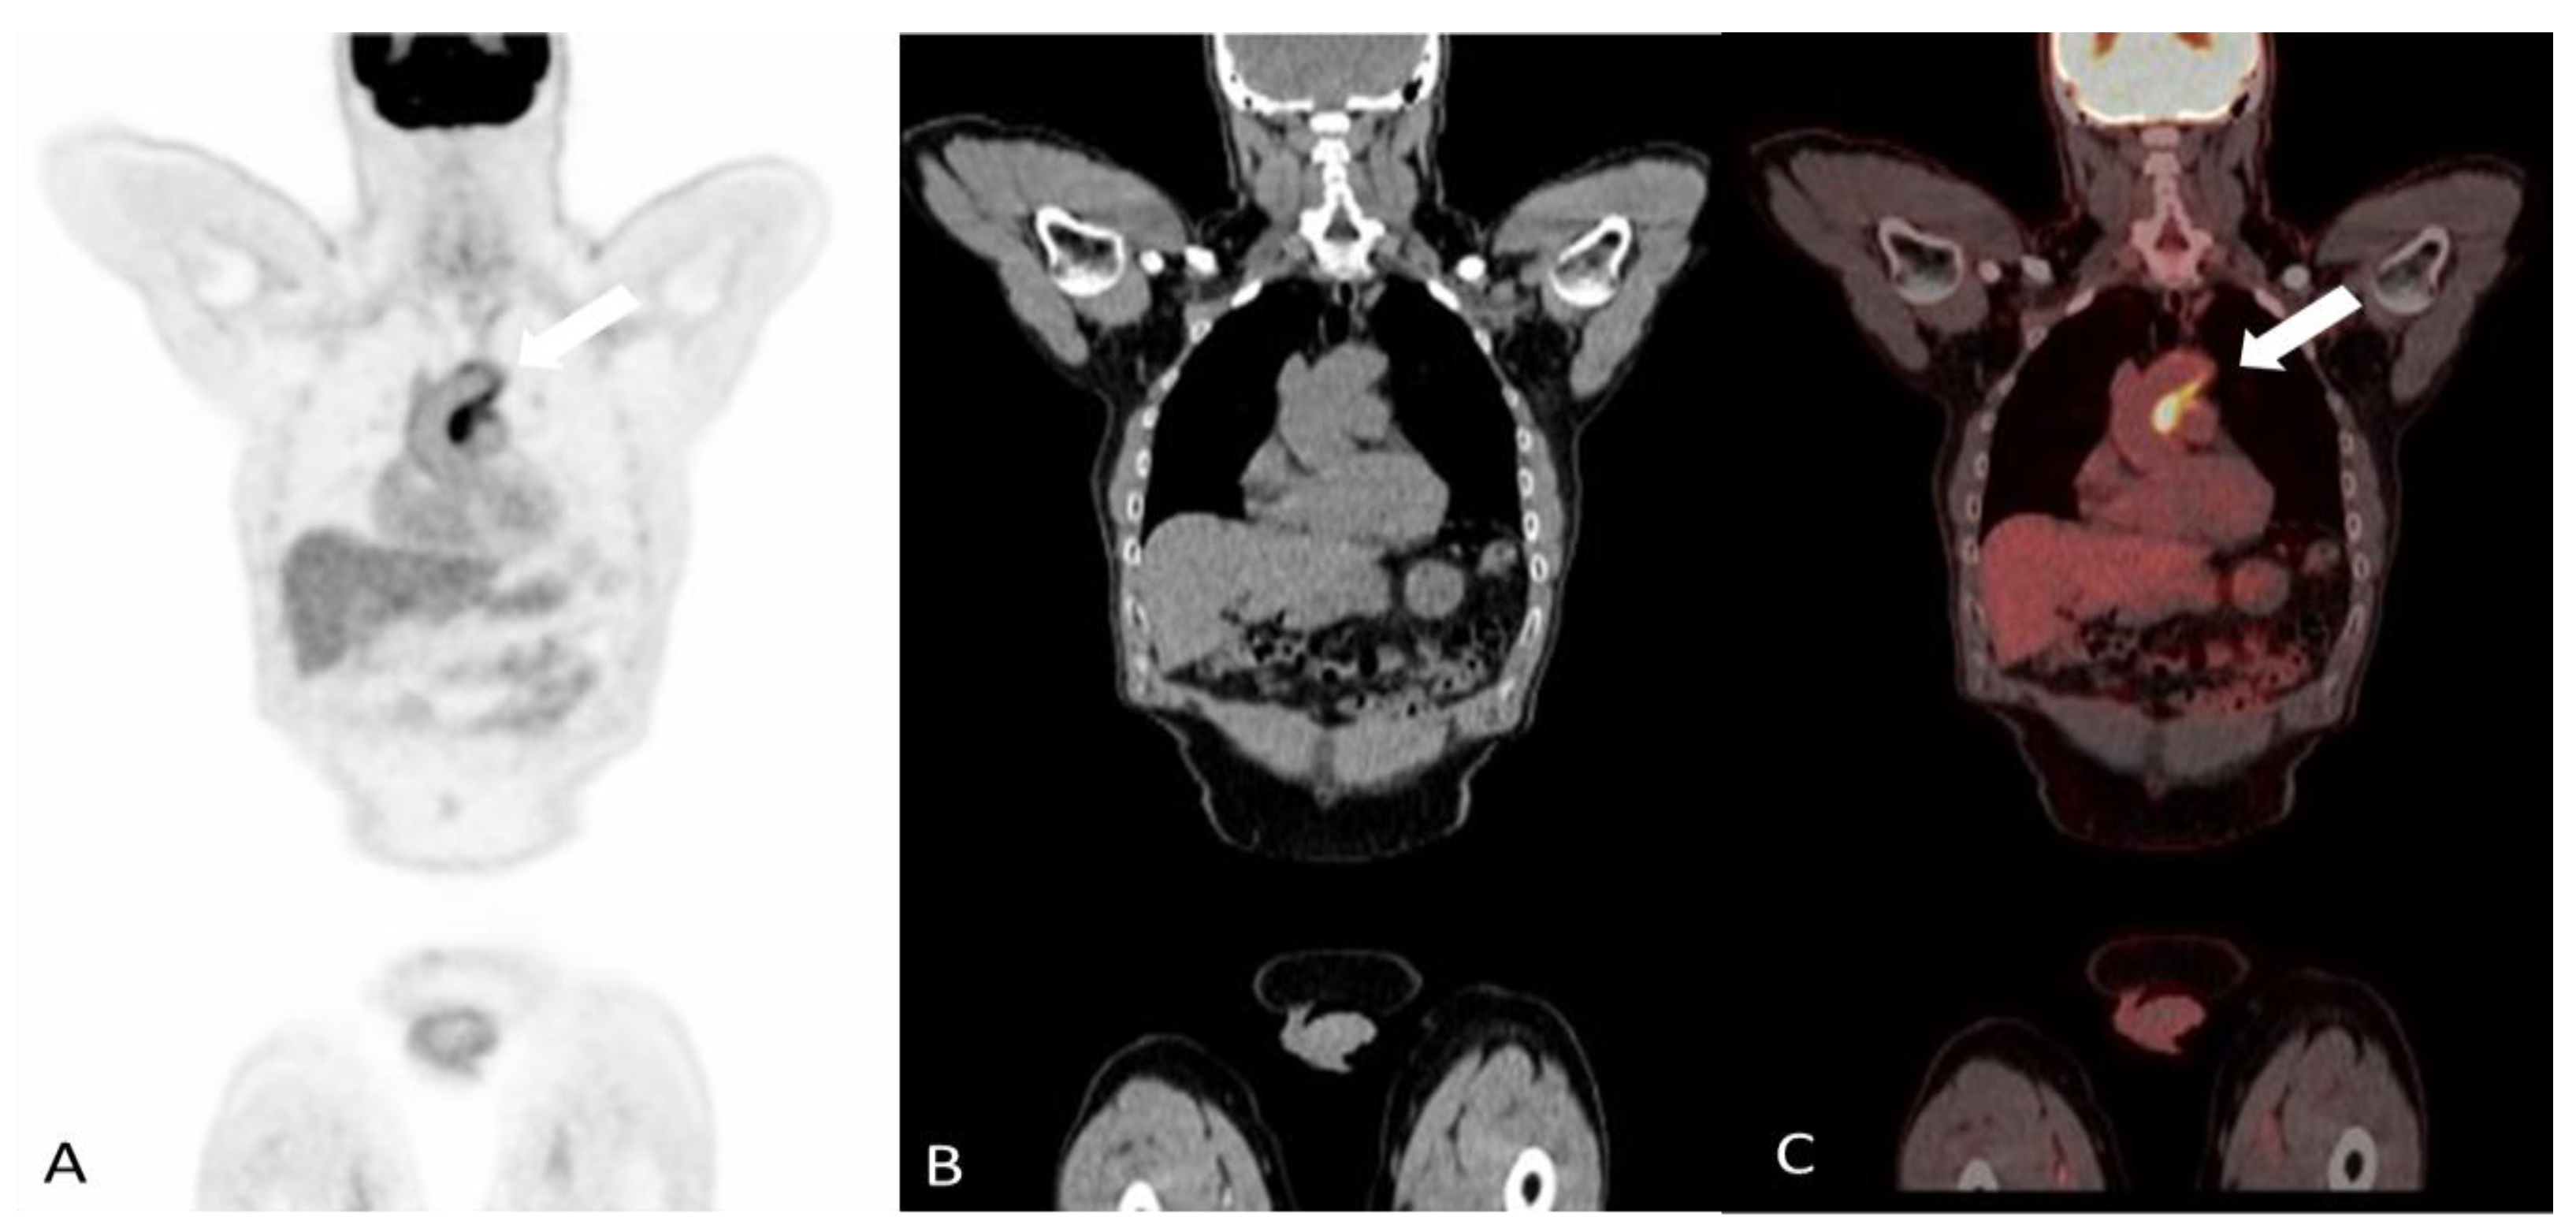

2.1.1. Giant Cell Arteritis

2.1.2. Takayasu’s Arteritis